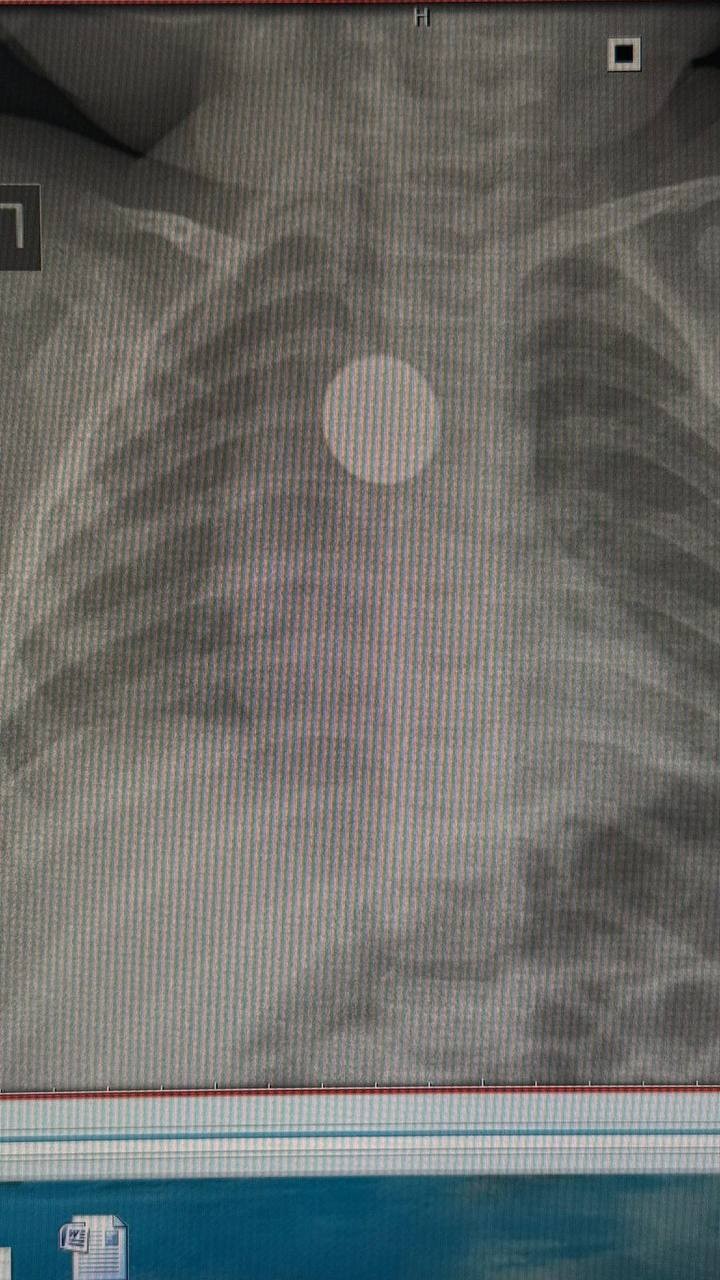

Монету в пищеводе обнаружили случайно. Девочку беспокоил кашель на протяжении месяца, врачи назначили рентген легких.

«Ребенка доставили в Якутск из Чурапчинского района. Монету обнаружили в области средней трети пищевода. Нам удалось вытащить инородное тело эндоскопом, ребёнок был под наркозом. У нее образовался поверхностный пролежень пищевода. Операция прошла хорошо, сейчас состояние девочки удовлетворительное», — рассказала ЯСИА Мария Еремеева.